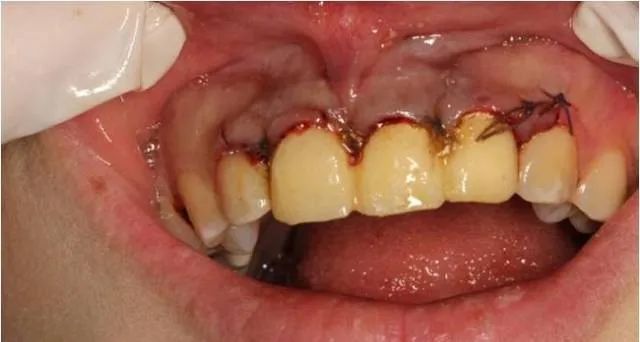

患者自述3年前上前牙因外伤折断在外院做烤瓷牙修复,现烤瓷修复体脱落。

经过检查发现,患者外露牙体组织不够,无法直接进行烤瓷牙重置。建议通过冠延长手术的方法,来使患牙的暴露量增加,然后再通过烤瓷牙进行牙齿的修复及改善牙龈形态的美观。与患者商议,表示接受该修复方案。

术前口内像

局麻下翻瓣

术中

翻瓣后清除炎性组织

颈缘骨修整

软组织修复整

间断缝合